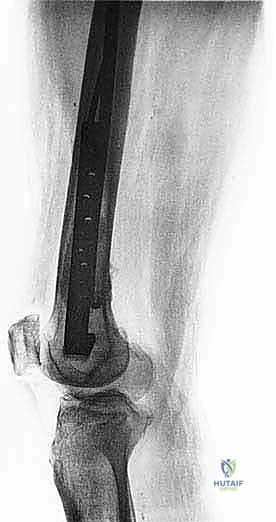

هذا الجزء يتسع ليشكل اللقمتين الفخذيتين (Condyles) اللتين تتمفصلان مع عظم الظنبوب (القصبة) لتكوين مفصل الركبة. النقائل في هذه المنطقة تؤثر بشكل مباشر على ميكانيكا الركبة وتسبب آلاماً شديدة عند ثني أو فرد الساق. الجراحة هنا تتطلب دقة متناهية للحفاظ على أربطة الركبة (الصليبية والجانبية) أو استبدال المفصل بالكامل بمفصل صناعي للأورام إذا كان التدمير العظمي واسعاً.

- الأشعة السينية العادية (X-rays): هي الخطوة الأولى دائماً. تظهر النقائل الحالة للعظم كبقع داكنة (ثقوب) في العظم، بينما تظهر النقائل البانية كبقع بيضاء كثيفة. الأشعة السينية ضرورية لتقييم خطر الكسر.

- التصوير بالرنين المغناطيسي (MRI): هو المعيار الذهبي لتقييم امتداد الورم داخل نقي العظم (النخاع) وإلى الأنسجة الرخوة المحيطة. الرنين المغناطيسي يوضح بدقة ما إذا كان الورم يقترب من المفاصل أو الأوعية الدموية.

- التصوير المقطعي المحوسب (CT Scan): يقدم تفاصيل ثلاثية الأبعاد لا مثيل لها لجودة القشرة العظمية المتبقية. يساعد الجراح في التخطيط لحجم المسامير أو الصفائح المطلوبة، وتقييم مدى تدمير العظم.